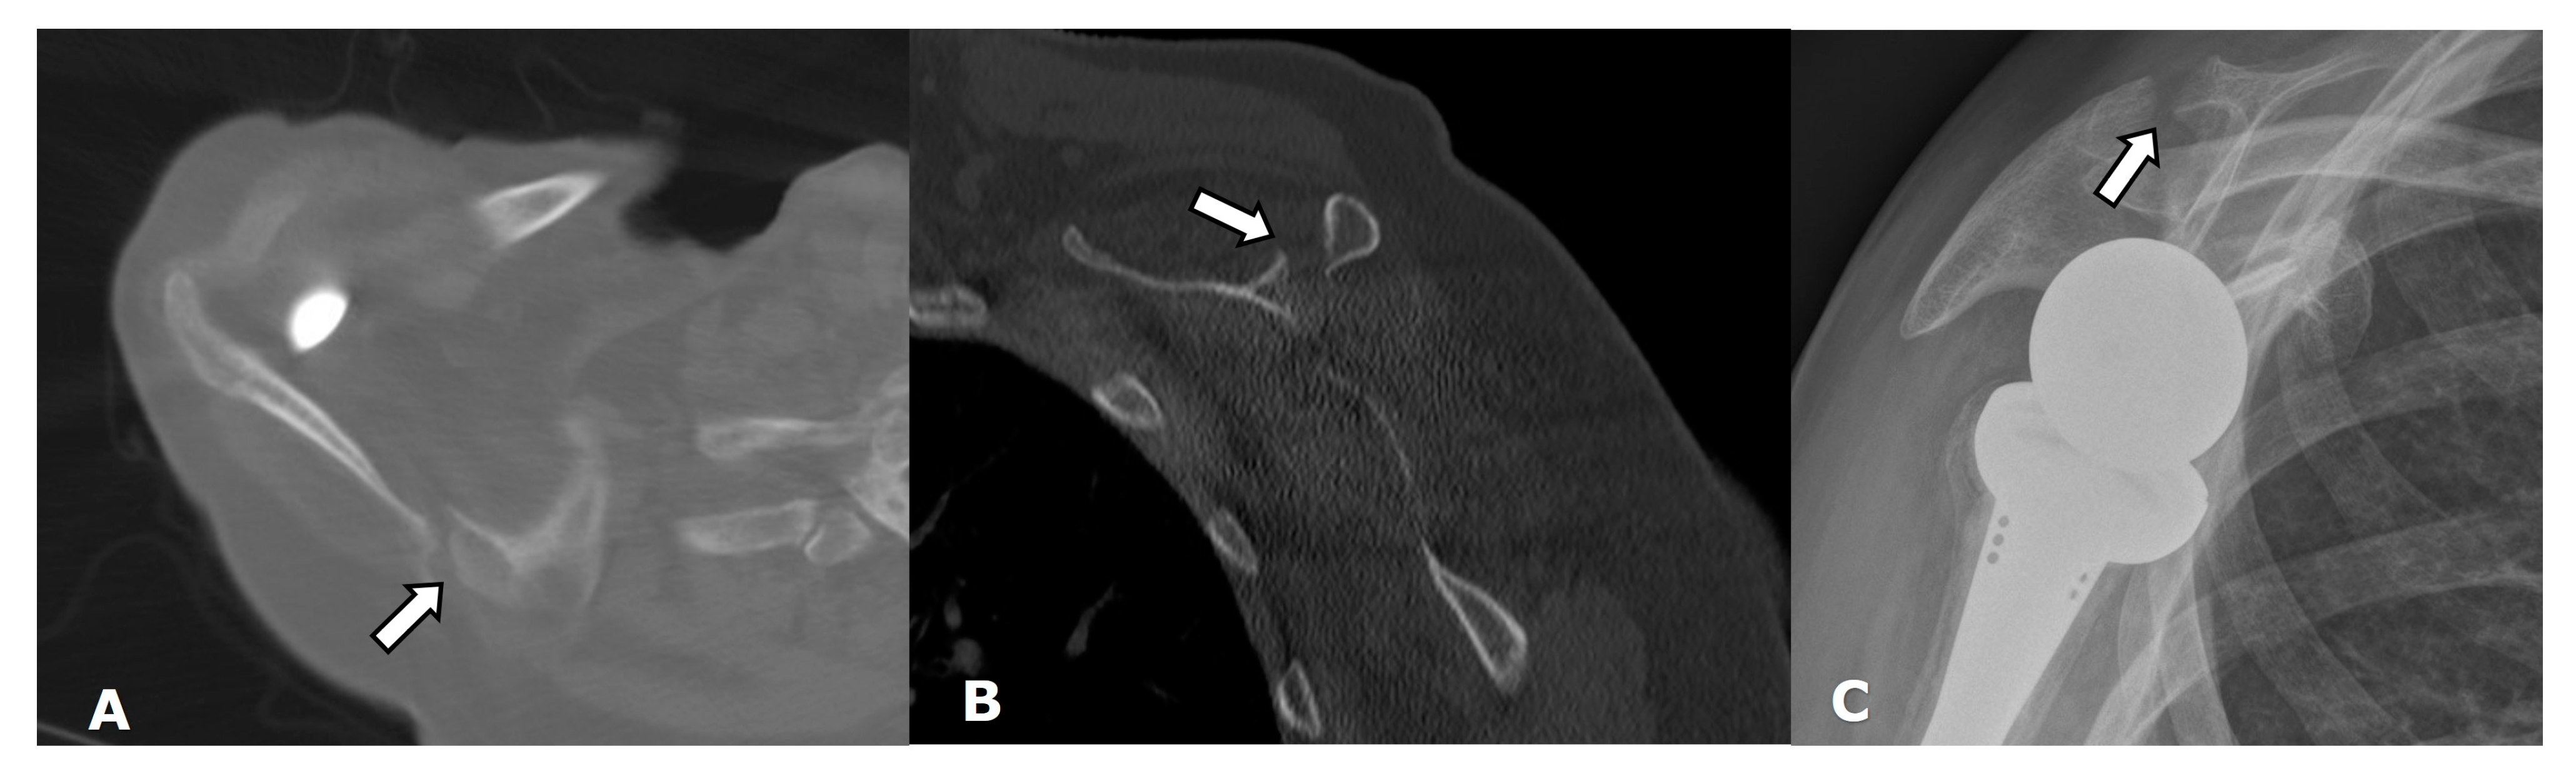

4.1. Imaging Techniques

4.2. General Complications

4.2.1. Loosening and Hardware Dissociation